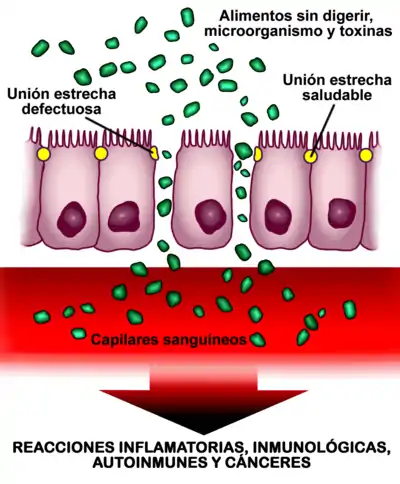

La gliadina es la fracción soluble en alcohol del gluten. Es una proteína rica en residuos de glutamina y prolina, y contiene la mayor parte de los productos tóxicos. Las moléculas de gliadina no digeridas, tales como la fracción alfa (que contiene 33 aminoácidos), son resistentes a la degradación por las secreciones gástrica, intestinal y pancreática. La existencia de un aumento de la permeabilidad en la barrera epitelial del intestino delgado debido al aumento de la señalización por parte de la zonulina (independientemente de la predisposición genética, es decir, tanto en celíacos como en no celíacos la gliadina aumenta la síntesis intestinal de zonulina ) permite que estos péptidos la atraviesen y reaccionen con las células presentes en la submucosa o lámina propia, lo cual desencadena una respuesta inflamatoria mediada por linfocitos T colaboradores tipo 1. Esta respuesta se caracteriza por la producción de un proceso inflamatorio, desencadenado por linfocitos CD4+ a nivel de la lámina propia o submucosa, que reconocen a los péptidos de la gliadina que son presentados por las células dendríticas ayudadas por moléculas HLA de clase II, del tipo DQ2 y DQ8. A continuación, se libera una serie de citoquinas pro-inflamatorias tales como el interferón gamma (IFN-γ) y el factor de necrosis tumoral alfa (TNF-α), entre otras, que favorecen la producción de la hiperplasia de criptas y la aparición de la lesión epitelial.[27]

Las lesiones que la celiaquía provoca en el intestino delgado de un celíaco no se limitan a la presencia de atrofia de las vellosidades intestinales, sino que con frecuencia consisten en cambios mínimos, con inflamación leve o moderada, especialmente en los niños mayores de dos años y los adultos.[19][50][51][52] [40]